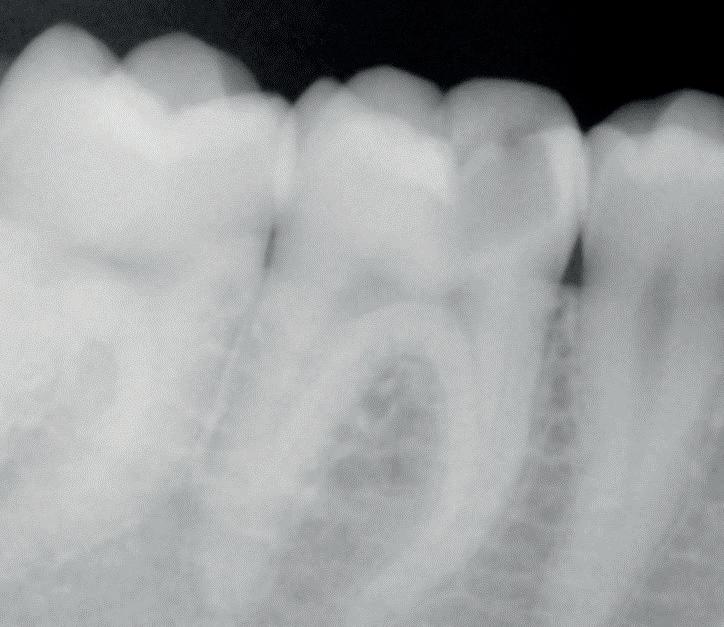

Throughout history, ground-breaking technologies have emerged which completely change people’s lives. These changes can be incredibly dramatic, and often unimaginable to those who came before them. For those who lived before the change, the technology, and the people who use it, can be difficult to understand. This kind of dramatic change is known as a ‘Singularity’ – originally a term used in maths, and now applied to the world of tech and artificial intelligence (AI) development.

technological developments and Singularity

Researchers believe it’s likely that AI will continue to evolve until it is capable of thinking at a human level, with some even believing that its power could continue to grow exponentially past this point. Systems which are designed to write code, like ChatGPT for example, may learn to constantly improve themselves, until they reach Singularity – the point at which they overcome human control. Some are particularly concerned about this, calling for the global management of AI development in order to limit the effects it might have and its ability to act and make decisions outside of its algorithm. While this conclusion is not a given, with the possibility that AI systems may not actually be able to improve themselves, it is interesting to consider the

current state and implementation of AI, the developments on the horizon, and imagine its potential in the future.

AI is already a useful tool in many aspects of life, with features such as Apple’s FaceID used by many every day, as well as digital voice assistants like Siri and Alexa used by people to answer quick questions. Algorithms which employ this technology are also used to work behind the scenes on social media, personalising the content each person is presented with. Similarly, search engines like Google use AI to scan the entire internet to produce the most relevant results. When we consider how often we all use these digital innovations on a daily basis, it’s clear to see how AI could be a force for good – helping to save us time, find the answers to questions, and complete tasks more efficiently than humans alone.

current use of ai in dentistry